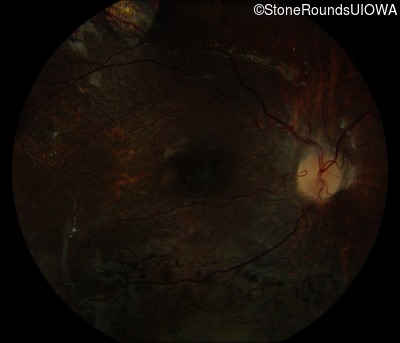

Fundus Photography - Right - 20/125 -1

Exemplar